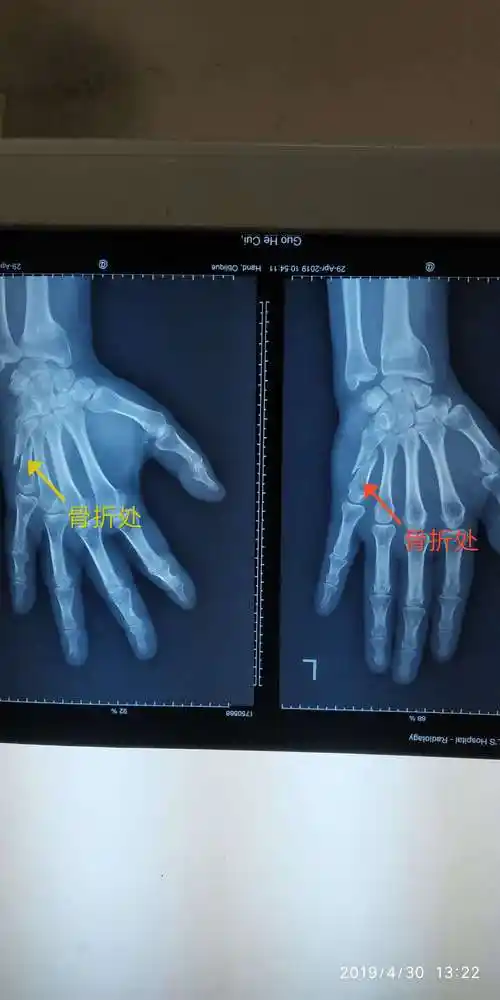

右中指撕脱性骨折(有x光片)

来医院急诊就诊,行x线片提示有右手中指第1节指骨近端骨折,涉及到关节